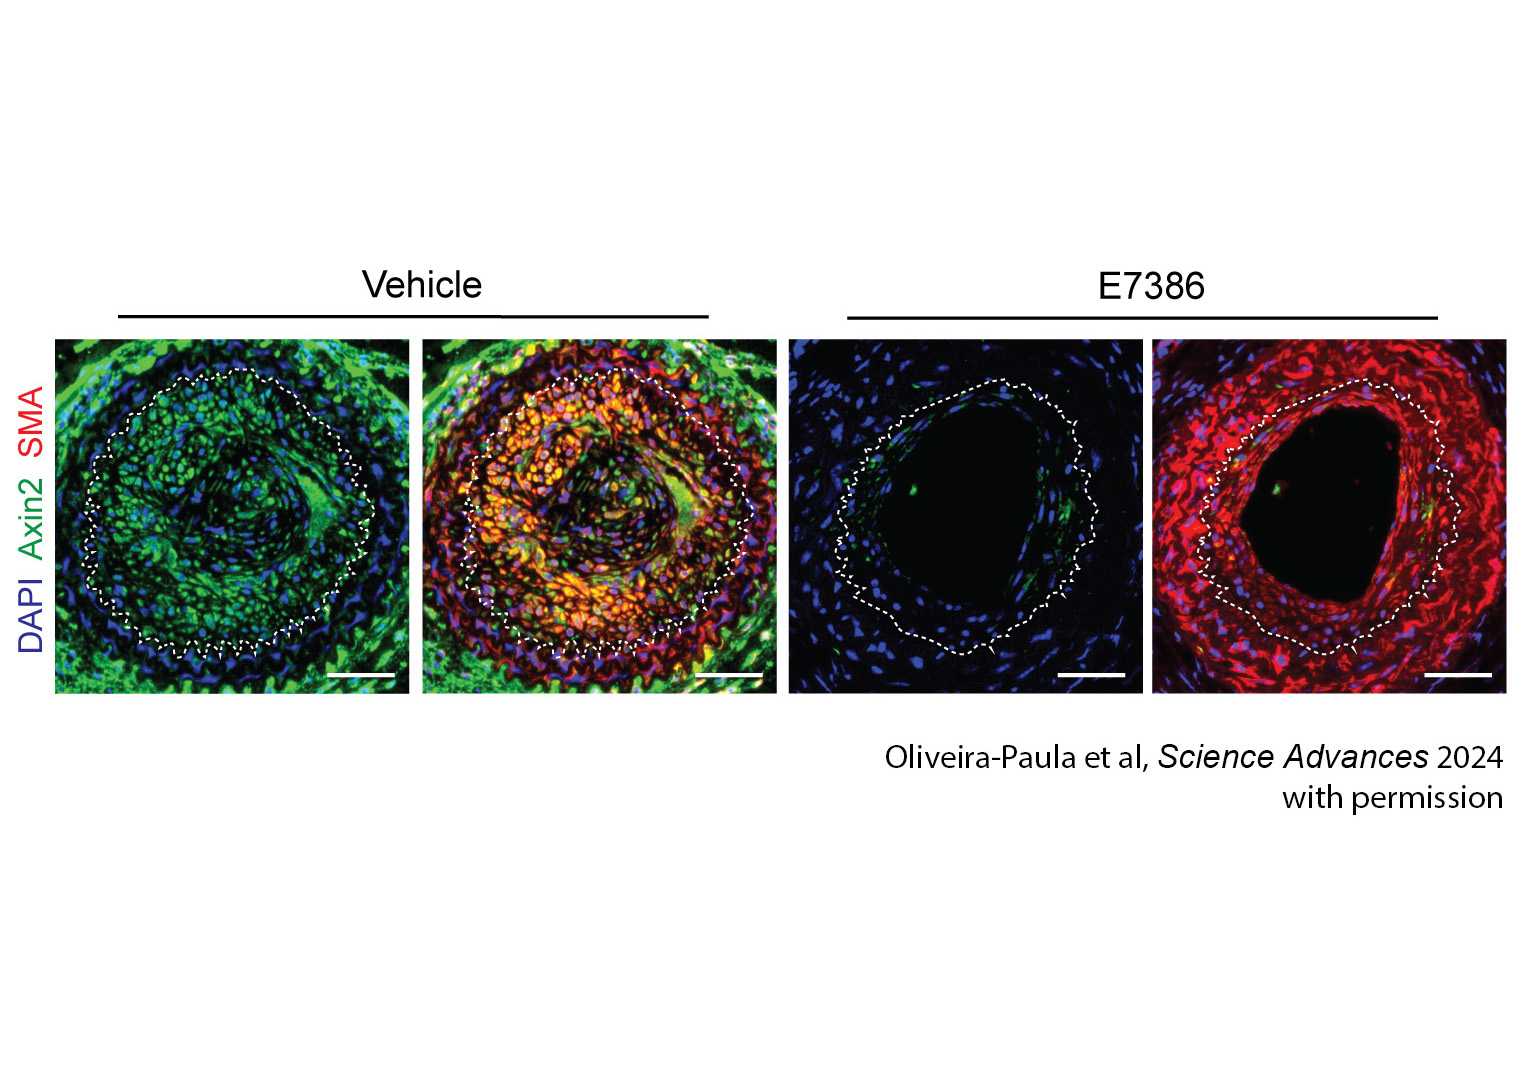

We participated in over 30 clinical trials in 2024, spanning from novel drugs through advanced devices for the treatment of heart failure, valvular heart disease and arrhythmias. Our investigators performed several first-in-human procedures that sought to offer better treatment options for patients with heart disease.